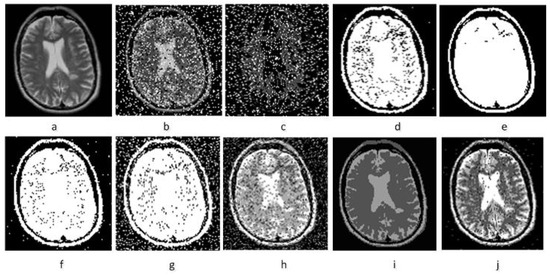

4.3.1. Denoising Experimental Results of MR Image